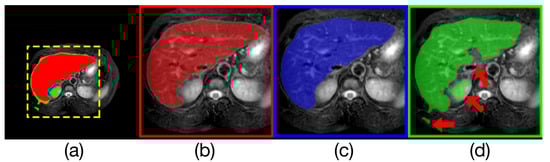

Table 4 compares the liver segmentation performance on MRI images, where Render U-Net had the best performance. The output of model and the manually annotated result are compared in Figure 11. Our proposed network increased IoU by over 0.0267 [20], increased the Dice coefficient by 0.0149, increased the precision by 1.3 percentage points, and increased the recall rate by 1.68 percentage points.

Figure 11. Comparison of model outputs and ground truth. (a) is composed of the other three figures above stacked from top to bottom, where the predicted extra areas are clearly seen. The red area in (b) is the manually annotated result. The blue region in (c) is the output of Render U-Net. The green region in (d) is the output of ANU-Net. Some areas with incorrect predictions are indicated with the red arrows in the figure.